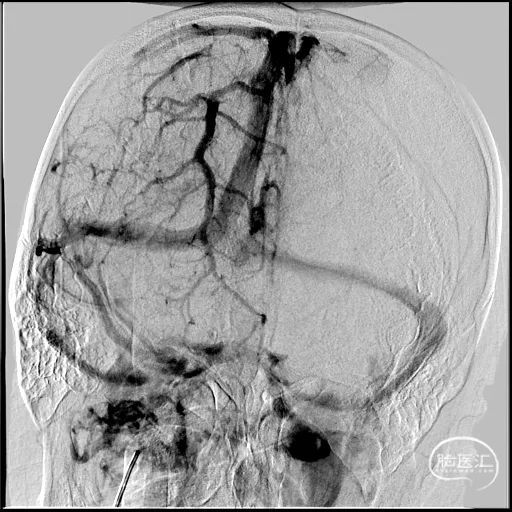

a) 取栓支架配合抽吸开通横窦右侧乙状窦:

图注5:

5A 右侧横窦乙状窦仍都栓子残留,反复抽吸无效,考虑栓子质地相对坚硬,拟置入取栓支架行拉栓操作

5B 经微导管置入Reco 6*30mm取栓支架,定位释放于栓子信号部位卡嵌栓子

5C 造影明确栓子已被取栓支架钳夹

5D 支架取栓配合ACE68抽吸后靶血管获得完全再通